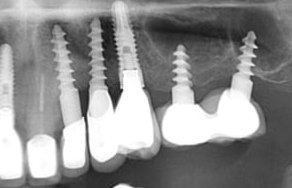

PACIENTE CON DOS IMPLANTES EN SECTOR ANTERIOR. CLINICA CERRADA

Hola, me ha venido un paciente sin piezas en el sector anterior y con dos implantes. La clínica suya esta cerrada y no sabe que implantes son. Necesito ayuda! [...]

Buenas tardes. Me gustaría saber el tipo de implante que está cargado. La paciente no ha podido pedir la informacion porqué me dice q donde se lo pusieron ha cerrado. [...]

Buenas tardes, me podríais ayudar con la marca del implante? esta sacada de la orto , pero si no se ve claro puedo hacerle una periapical, muchas gracias de antemano

Necesito ayuda para identificar que implantes para restaurar las coronas que están con la porcelana fracturada por favor.

Buenas tardes, ¿me podria algun decir que tipo de conexion y marca de implante es? muchisismas gracias de antemano!

Por favor! Alguien sabe que marca de implante es? Gracias!